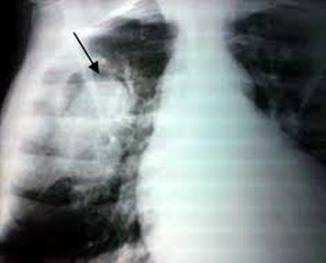

Radiología:

Cardiomegalia

Radiografía: cardiomegalia con hipertensión venosa pulmonar